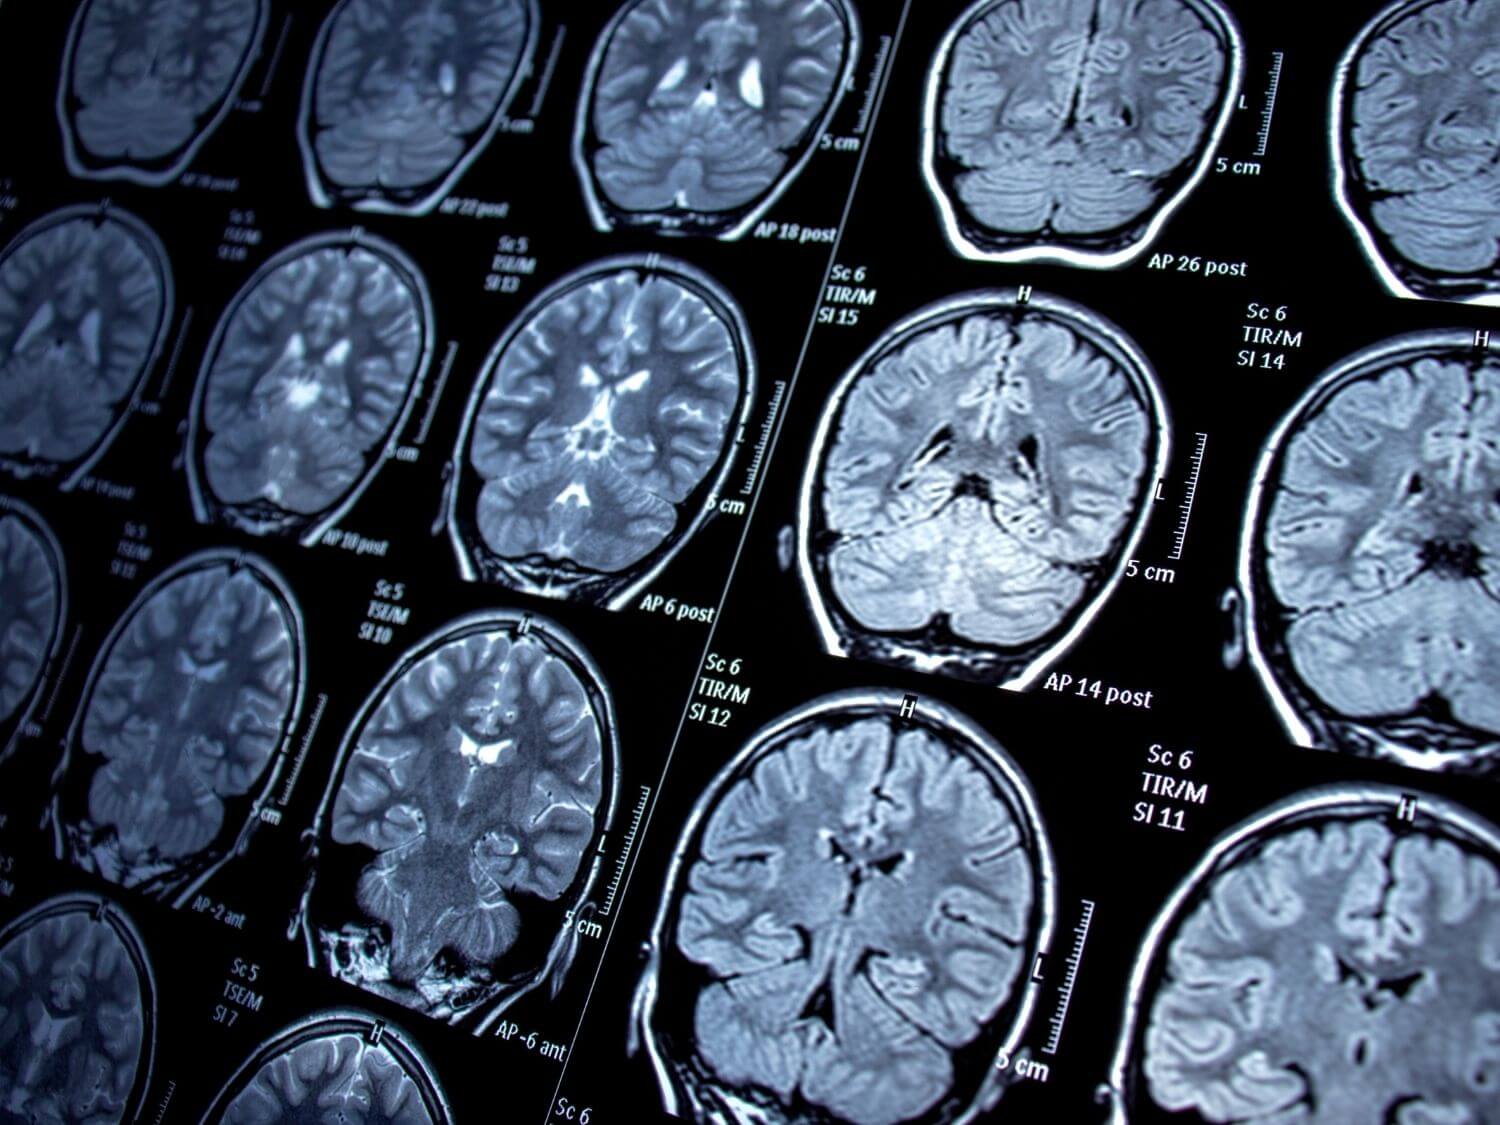

뇌전증은 기본적으로 뇌의 신경세포가 갑작스레 과도한 흥분 상태가 되면서 의식을 잃거나, 발작 증상을 일으키는 뇌 질환을 말합니다.

예를 들자면 팔의 움직임을 조절하는 뇌 부위에 이상이 생기면 한쪽 팔만 떠는 증상이 나타날 수도 있고, 측두엽 부위에서 이상이 생기면 의식을 상실하고 입맛을 다시는 증상이 나타나기도 합니다.

이와 같이 뇌전증으로 인해 나타나는 증상은 이상이 생긴 뇌의 부위와 강도에 따라서 다양한 양상으로 나타나게 됩니다.